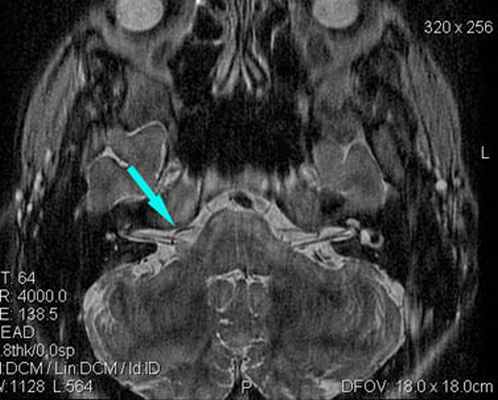

Определяется близкое расположение артериального сосуда и лицевого нерва (указано стрелкой), что может являться причиной гемифациального спазма

Визуализируется близкое расположение артериального сосуда и лицевого нерва (указано стрелкой), что может являться причиной гемифациального спазма